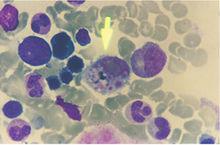

血液透析HL Van Epps等研究了針對HTN病毒感染的人T淋巴細胞的反應,包括針對核蛋白或G1蛋白的和T細胞系,部分針對核蛋白的 T細胞系與無名病毒核蛋白有交叉反應,而針對核蛋白或G1蛋白的 T細胞系與無名病毒蛋白沒有交叉反應。這種引起不同漢坦病毒病(HFRS和HPS)的毒株,人T細胞系的交叉反應在病理研究和疫苗研製中具有重要意義。F.A.Ennis等進行的另一項研究,從HPS病人血中分離和 T細胞系,有些細胞系識別的區域在不同漢坦病毒株間相對保守,但有些T細胞系不能識別漢坦病毒單一的胺基酸改變,另一些T細胞系能識別關係較遠的分離株,如安第斯和普馬拉病毒的相應區域。C.Mansilla等對安第斯病毒致死病人屍檢結果表明,Andes-HPS和SNV-HPS引起的病理改變和病毒抗原分布相似,但Andes-HPS病例發現有充血性心肌炎和Ⅱ型肺單核細胞活性,並有較多的肝染色。M.Bharadwaj等從Andes-HPS病人氣管中檢出病毒RNA,認為安第斯病毒可能在人-人間傳播。還有報告研究了血組胺和緩激肽、類脂過氧化物、血管加壓素、溶酶體、紅細胞膜腺苷三磷酸酶等在HFRS病理改變中的作用。S.C.St Jeor等研究了SN病毒在鹿鼠體內的持續感染,感染後幾周至幾個月內,隨著抗體水平的增高,血清中病毒消失,其他組織中病毒減少。Karen L.Hutchinson等研究了BCC病毒在刺毛棉鼠體內的感染,感染後前幾周,定量PCR在除血液外的各組織中檢出病毒cRNA,以後病毒cRNA減少,感染5個月後只在腦內檢出;感染後1周血液中存在感染性病毒,2周時達高峰,3周時顯著減少;感染後5個月在腎上腺、肝、腎、睪丸仍可低水平檢出感染性病毒;感染後70d內尿中可分離到病毒;感染14d後可檢出BCC抗體。楊守敬等的研究表明,HFRS的休克和出血引起的局部缺血可以導致熱休克反應,在病人組織中表達72KD和73KD的熱休克蛋白,保護組織細胞免於損傷。他們的另一項研究,通過增生細胞核抗原以及細胞分裂中波形蛋白抗體的檢測表明,在HFRS組織損傷過程中,存在細胞的再生和DNA的修復,修復程度與損傷的嚴重程度有關。